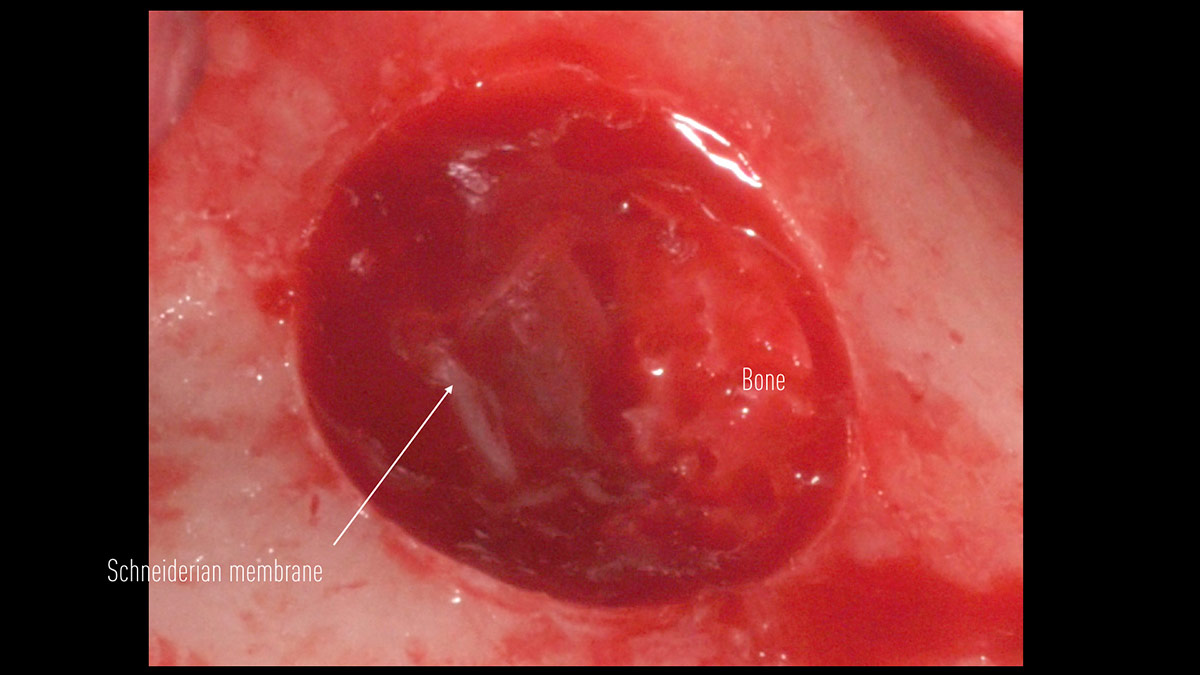

Delayed implant placement; sinus floor elevation by means of lateral approach and implant placement with GBR. Case report by Irfan Abas, M.Sc.